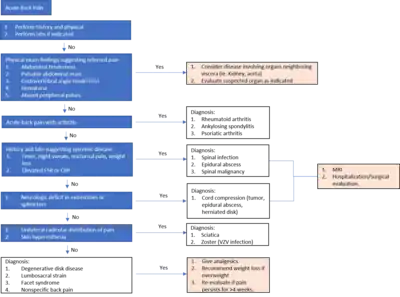

Diagnosis

Initial assessment of back pain consists of a history and physical examination.[35] Important characterizing features of back pain include location, duration, severity, history of prior back pain and possible trauma. Other important components of the patient history include age, physical trauma, prior history of cancer, fever, weight loss, urinary incontinence, progressive weakness or expanding sensory changes, which can indicate a medically urgent condition.[35]

Physical examination of the back should assess for posture and deformities. Pain elicited by palpating certain structures may be helpful in localizing the affected area. A neurologic exam is needed to assess for changes in gait, sensation and motor function.

Determining if there are radicular symptoms, such as pain, numbness or weakness that radiate down limbs, is important for differentiating between central and peripheral causes of back pain. The straight leg test is a maneuver used to determine the presence of lumbosacral radiculopathy, which occurs when there is irritation in the nerve root that causes neurologic symptoms such as numbness and tingling. Non-radicular back pain is most commonly caused by injury to the spinal muscles or ligaments, degenerative spinal disease or a herniated disc.[11] Disc herniation and foraminal stenosis are the most common causes of radiculopathy.[11]

Imaging of the spine and laboratory tests is not recommended during the acute phase.[19] This assumes that there is no reason to expect that the patient has an underlying problem.[36][19] In most cases, the pain subsides naturally after several weeks.[36] People who seek diagnosis through imaging are typically less likely to receive a better outcome than are those who wait for the condition to resolve.[36]

Imaging

Magnetic resonance imaging (MRI) is the preferred modality for the evaluation of back pain and visualization of bone, soft tissue, nerves and ligaments. X-rays are a less costly initial option offered to patients with a low clinical suspicion of infection or malignancy, and they are combined with laboratory studies for interpretation.

Imaging is not warranted for most patients with acute back pain. Without signs and symptoms indicating a serious underlying condition, imaging does not improve clinical outcomes in these patients. Four to six weeks of treatment is appropriate before consideration of imaging studies. If a serious condition is suspected, MRI is usually most appropriate. Computed tomography is an alternative if MRI is contraindicated or unavailable.[37] In cases of acute back pain, MRI is recommended for those with major risk factors or clinical suspicion of cancer, spinal infection or severe progressive neurological deficits.[38] For patients with subacute to chronic back pain, MRI is recommended if minor risk factors exist for cancer, ankylosing spondylitis or vertebral compression fracture, or if significant trauma or symptomatic spinal stenosis is present.[38]

Red flags

Imaging is not typically needed in the initial diagnosis or treatment of back pain. However, if there are certain "red flag" symptoms present, plain radiographs (X-ray), CT scan or magnetic resonance imaging may be recommended. These red flags include:[43][11]